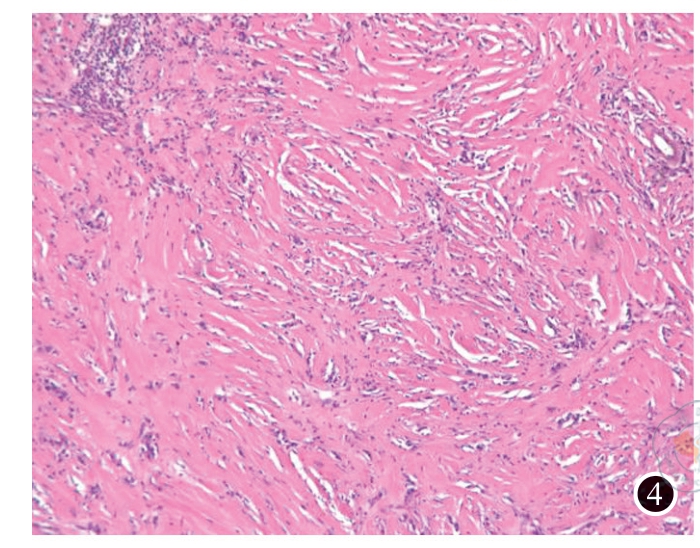

图1 孤肾合并肾炎性肌纤维母细胞瘤患者术前CT平扫

图7 肾炎性肌纤维母细胞瘤免疫组化(MSA×200) 注:图1中左肾下极可见一结节样密度增高影,凸向肾脏轮廓外,大小约 1.4 cm×1.1 cm(箭头所指)。图2可见左肾下极病变各期呈持续强化,边缘光滑(箭头所指)。图3可见肿瘤大小约为1.5 cm×1.1 cm×1.1 cm,切面灰白色,实性,质地中等。图4可见肾脏组织中见梭形细胞肿瘤,肿瘤细胞由纤维母细胞及肌纤维母细胞构成,细胞无明显异型性,呈束状、交织状排列,部分玻璃样变,淋巴细胞、浆细胞及组织细胞灶状聚集。图5可见肾炎性肌纤维母细胞瘤肿瘤细胞SMA呈阳性表达。图6可见肾炎性肌纤维母细胞瘤肿瘤细胞Desmin呈阳性表达。图7可见肾炎性肌纤维母细胞瘤肿瘤细胞MSA呈阳性表达